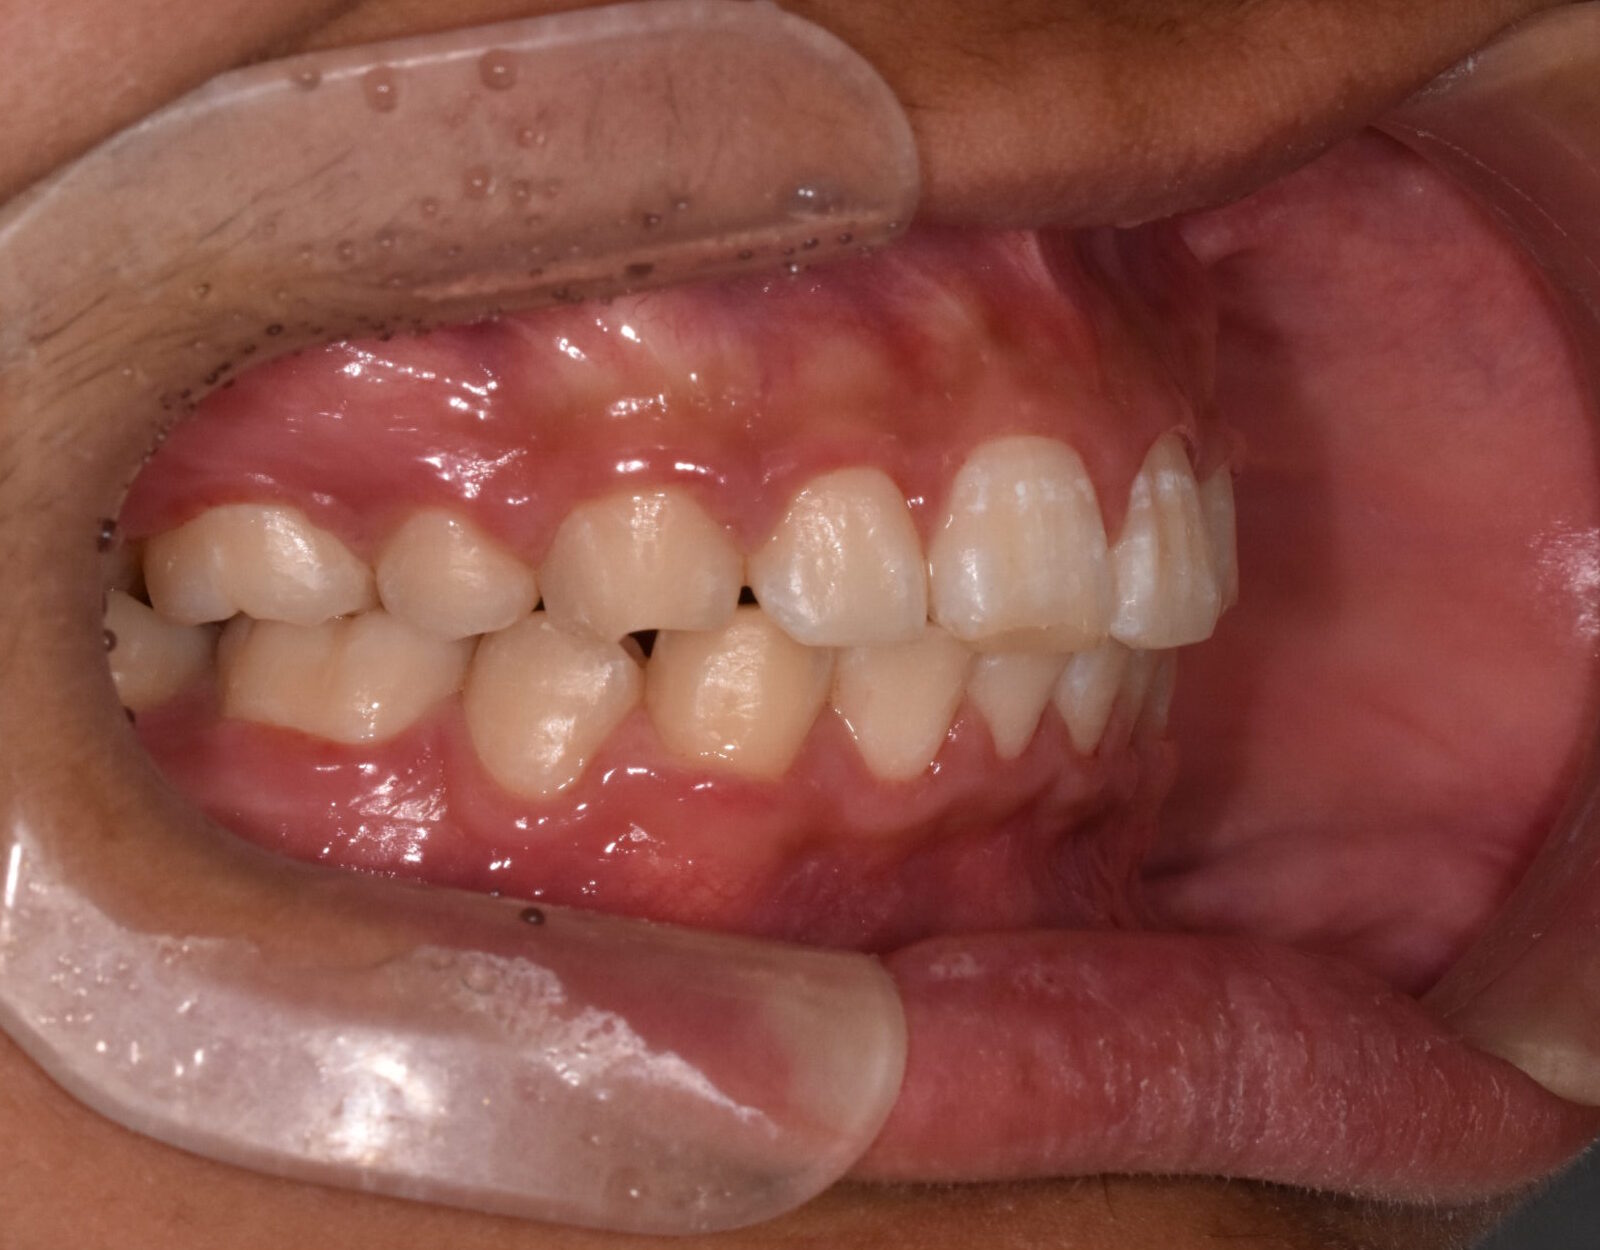

過蓋咬合・叢生 13歳男性

13歳9ヶ月 男性

治療後

【診断】叢生、過蓋咬合

【治療方法】上下両側第一小臼歯抜歯、ワイヤー治療期間3年間、上顎口蓋にTPA(トランスパラタルアーチ)を行いました。